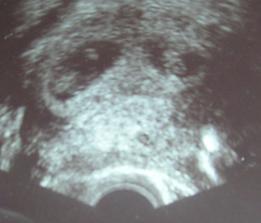

18.září jsme byli na našem 1.IVF... a 8.den od ET se mi "zjevily" nádherné // 🙂... přeju si,aby se všechno vyvíjelo dobře... 29.9 11.den po ET mi pro zhoršení OHSS provedli punkci Douglasova prostoru a odsáli 2 litry žlutého ascitu ☹ Nicméně se mi ulevilo 🙂 HCG ten den 259... 6.10 kontrola HCG - 2950 (18.den od ET)... 10.10 UTZ - čekáme DVOJČÁTKA 🙂 🙂 🙂... 17.10 krvácení a následná hospitalizace, UTZ - dvojčátkům bijí srdíčka, 20.10 HCG - 56000, 25.10 propuštění z nemocnice... 31.10 poslední kontrola v CARu, dvojčátka mají 2 a 2,1 cm... 11.11 UTZ - dvojčátka mají 3 cm... 24.11 UTZ - dvojčátka mají 9 cm (ale moc se mi to měření nezdá, ve čtvrtek na screeningu se ukáže pravda, čeká nás 3D 🙂) 27.11 screening I.trimestru - miminka jsou zdravá, od hlavičky po prdelku mají 7 cm... 19.12 3D - miminko "A" je chlapeček, "béčko" chce zůstat zatím v utajení 🙂 tak snad příště 🙂... 8.1 3D - miminko "B" je holčička 🙂 19.1 echokardiografie - obě srdíčka jsou zdravá 🙂 20.1 screening II.trimestru - vše OK, miminka mají 360 a 364 gramů 🙂 26.1 UTZ - chlapečkovi se ztratil pindík a najednou čekáme 2 holčičky 🙂) Doufám, že už je to definitivní 🙂) 19.2 UTZ 3D4 - holčičky potvrzeny!!! 🙂 mají každá téměř 800 gramů! 🙂 20.3 UTZ - holčičky mají 1700 a 1800 gramů! 8.4 UTZ - holky mají neuvěřitelné váhy 2415 a 2600 gramů! 11.5 nástup do nemocnice... 11.května ve 20,03 se nám akutním císařským řezem narodila Eliška (2970/48) a o minutu později Nelinka (3200/50).Jsme nejšťastnější rodiče na světě! 🙂